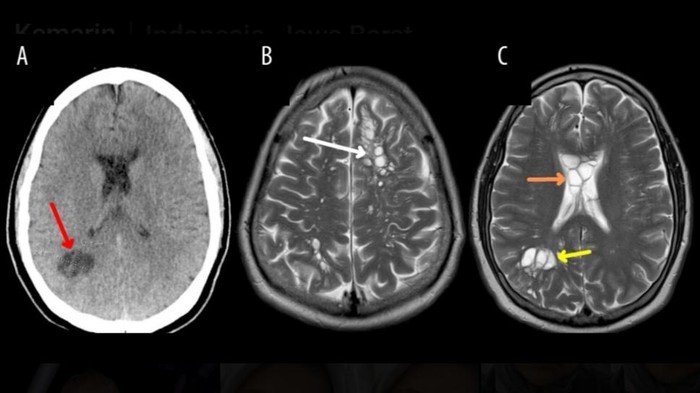

Dalam jurnal yang dikutip dari Live Science, dokter langsung memeriksa tanda-tanda vital pada pasien, tetapi tidak menunjukkan adanya kelainan. Setelah melakukan CT scan pada otaknya, dokter melihat adanya banyak lesi mirip kista yang tersebar di kedua hemisfer atau kedua bagian besar otak.

Secara spesifik, pertumbuhan ini muncul di substansia alba organ tersebut, yakni jaringan terisolasi yang memanjang dari sel-sel otak.

Pasien segera dirawat di rumah sakit untuk melakukan konsultasi bedah saraf. Hasil MRI pun mendukung apa yang terlihat di CT scan.

Bahkan, dokter melihat adanya penumpukan cairan di sekitar kista di otak pria tersebut. Karena menduga adanya parasit, departemen bedah saraf merujuk pasien ke spesialis penyakit menular dan melakukan sejumlah tes.